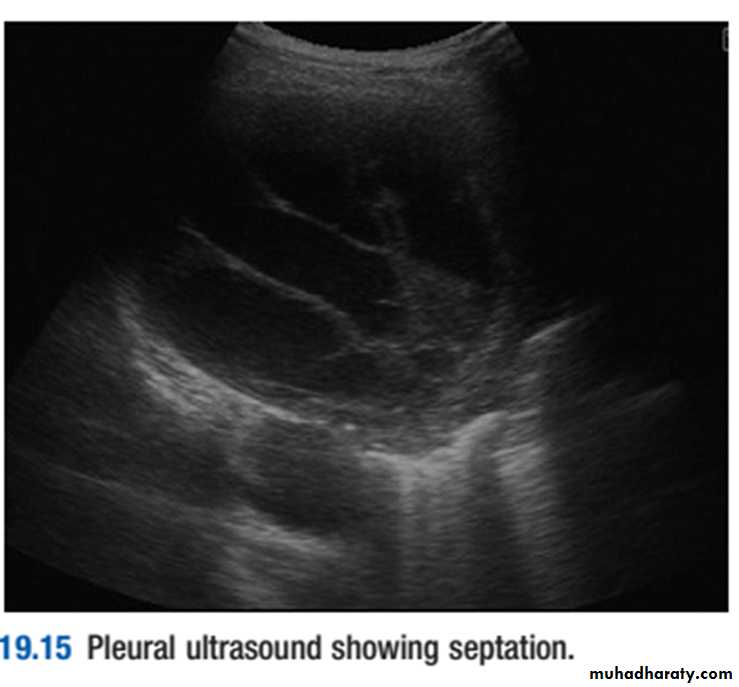

Chest X-ray appearances may be indistinguishable from those of pleural effusion, although pleural adhesions may confine the empyema to form a ‘D’-shaped shadow against the inside of the chest wall .When air is present as well as pus (pyopneumothorax), a horizontal ‘fluid level’ marks the air/liquid interface.Ultrasound shows the position of the fluid, the extent of pleural thickening and whether fluid is in a single collection or multiloculated, containing fibrin and debris .